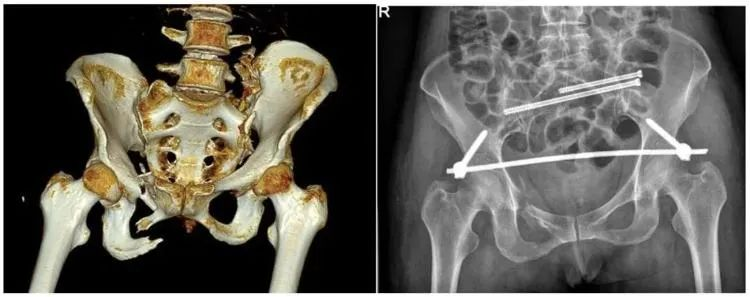

二、穩定性骨折&不穩定性骨折

另外,我們根據骨盆骨折是否穩定可以分為穩定性的骨折和不穩定性的骨折。如果是不穩定性的骨折醫生可能會建議病人進行手術治療,把不穩定性的骨折變成穩定性的骨折。

普愛醫療推出的大平板一體式C形臂PLX119C,配置30cm×30cm平板探測器,大視野,能夠呈現更多圖像細節,對于諸如骨盆雙側骨折類型手術或骨盆后環內固定術具有應用優勢,一次曝光可獲取全部骨折部位影像,可簡化曝光流程,提高手術效率。